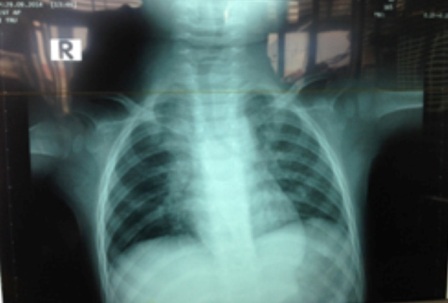

Tại đây, qua chẩn đoán hình ảnh bác sĩ xác định bệnh nhi bị xẹp thùy dưới phổi phải, dị vật là hạt mãng cầu nằm bít tắc hoàn toàn phế quản gốc phải. Bệnh viện lập tức mở cuộc hội chẩn và xác định đây là ca bệnh rất khó xử trí vì dị vật to tròn, trơn láng, chiếm hết lòng phế quản, không còn khoảng trống để đưa dụng cụ vào gắp dị vật. Khí quản của bệnh nhi quá bé, việc thực hiện phương pháp nội soi rất khó khăn, song nếu không khẩn trương can thiệp bệnh nhi có thể tử vong.